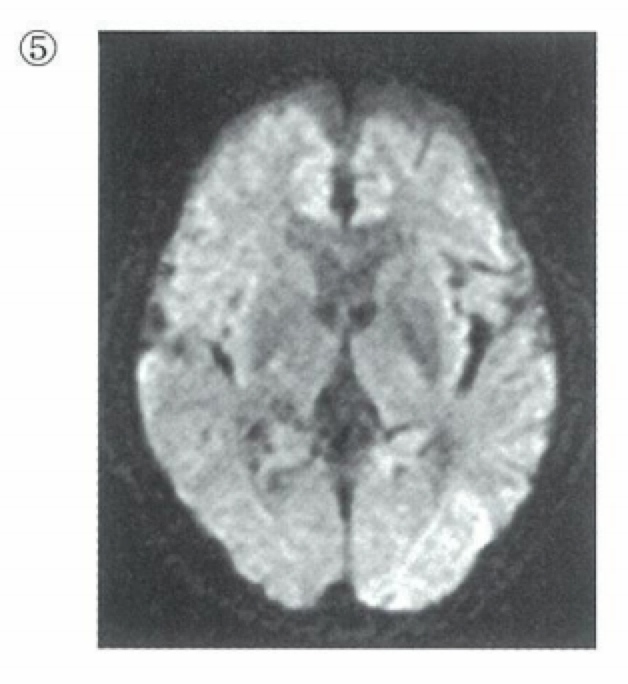

- 虚血→ミトコンドリアATP産生能↓→Na-Kポンプ↓→細胞外Na流入&細胞外水流入→水の動き制限(ブラウン運動小)→高信号

拡散強調画像(かくさん(きょうちょう)がぞう、diffusion (weighted) image, DWI)とは、核磁気共鳴画像法 (MRI) のシーケンスの一種で、水分子の拡散運動を画像化したものである。通常用いられるスピンエコー法のパルス系列では拡散による信号の減衰は無視できるが、大きな傾斜磁場が長時間にわたって印加されると、その間の各磁化ベクトルの移動によって生じる位相のずれが無視できなくなり、拡散が活発な領域ほど低信号として現れる。こうして得られた画像を拡散強調画像とよぶことがある。また、スピンエコー法のパルス系列において、傾斜磁場の強さや印加時間を変えることによりディフェージングの効果を付けて得られた複数の画像から、見かけ上の拡散係数 (apparent diffusion coefficient, ADC) を求めて画像化することができ、これを拡散(係数)画像 (ADC map) とよぶ。

コンピュータ断層撮影 (CT) で描出できない、超急性期または急性期の脳梗塞診断に非常に有用で、救急医療で広く用いられている。また脳腫瘍の一部(類上皮腫とくも膜嚢胞との鑑別)、脳膿瘍の診断にも有用である。

- CTでは発症早期の所見は取りづらく(early CT signは除く)、12-24時間後に低吸収が出現するため、拡散強調画像(DWI)による発症1-3時間後の高信号をとらえるのが早期診断に有用である。

- 画像検査では超急性期には拡散強調画像が有用。CTではearly CT signを確認する。

- 拡散強調画像:超急性期で梗塞部が高信号を呈する。